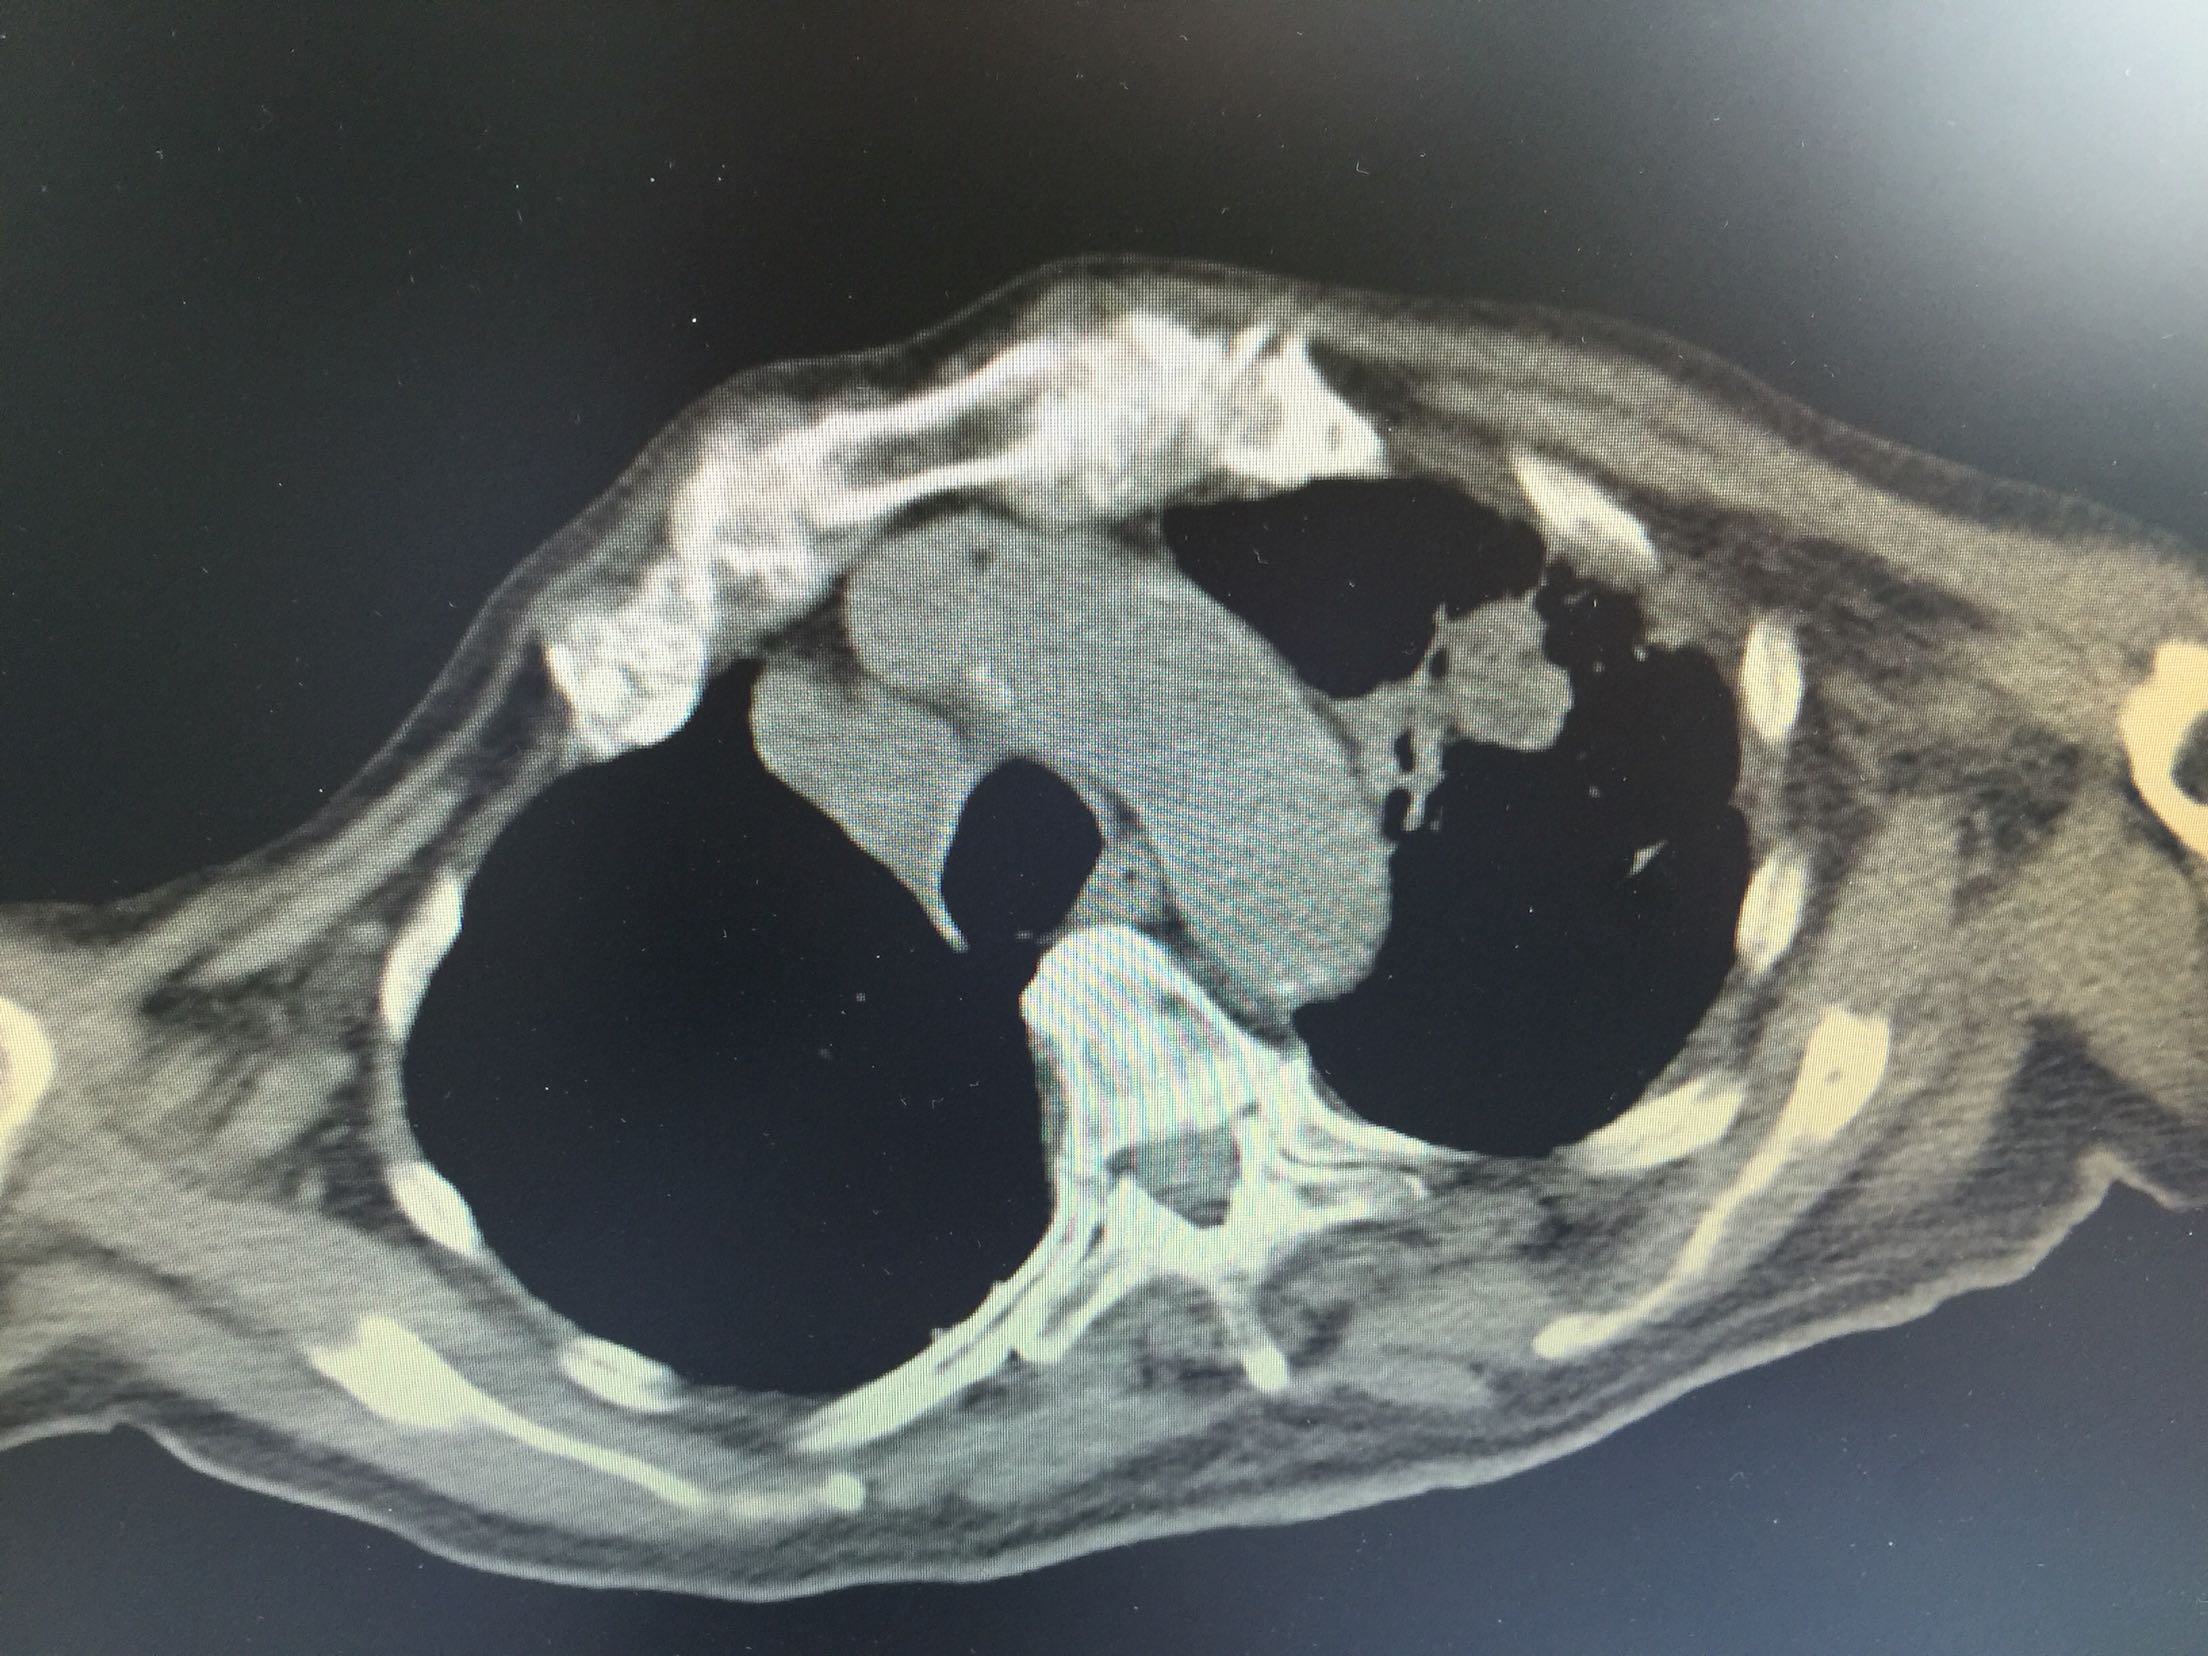

肺癌脑转移1例。

女,81岁,以“意识障碍1天”入院。

查体:浅昏迷,双眼向左侧凝视,双瞳孔等大正圆,直径3.0mm,对光反射灵敏,四肢不自主运动,肌张力正常,腱反射卄,Babinski征R-L-,脑膜刺激征阴性。

1.肺癌脑转移。 治疗:营养神经、脱水、抗感染、化痰、维持离子平衡治疗。